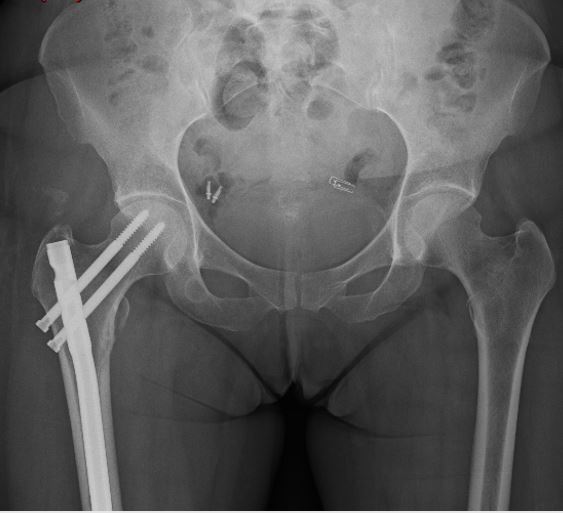

Trauma

Trauma is the largest cause of bad outcomes in young Australians, so it is critical that it is treated by well trained professionals. The John Hunter Hospital is the highest volume centre for multiply injured patients in New South Wales.

Dr Tarrant has experience training in complex trauma of the skeleton in both the immediate and delayed setting.